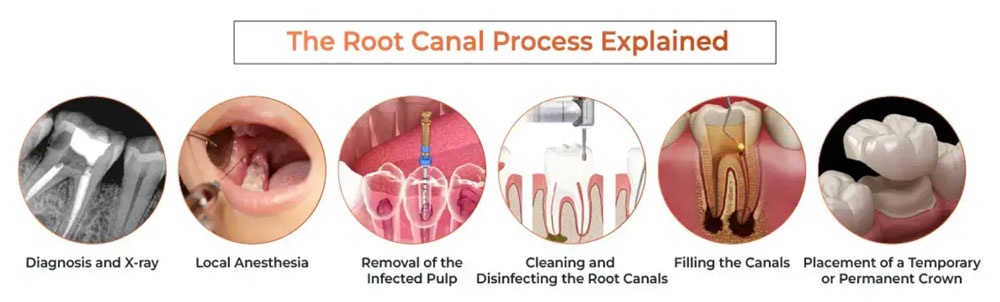

Root canal treatment is a procedure used to remove infected or inflamed pulp from inside a tooth. If left untreated, this condition can lead to a painful abscess. By performing root canal treatment, the tooth can often be saved, avoiding the need for extraction and preserving your natural smile.